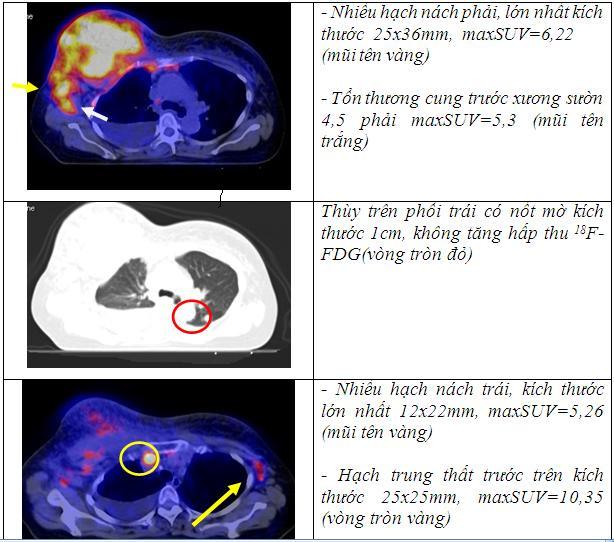

Hình 2: Hình ảnh siêu âm vú: tổn thương thâm nhiễm toàn bộ vú phải (hình A), nang vú trái (hình B)

• Siêu âm vú: Tổn thương thâm nhiễm toàn bộ vú phải, nang vú trái